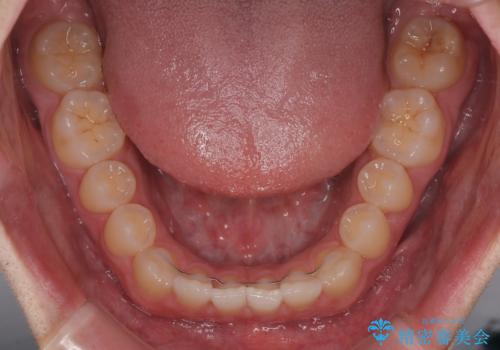

- インビザラインモデレート

- 11ヶ月

- 5-10回

患者様は「できるだけ目立たない矯正治療」を希望されていたため、インビザラインを用いた治療計画を立案しました。

インビザラインは透明で装着していても気づかれにくく、日常生活やお仕事への影響を最小限に抑えながら治療を進めることが可能です。